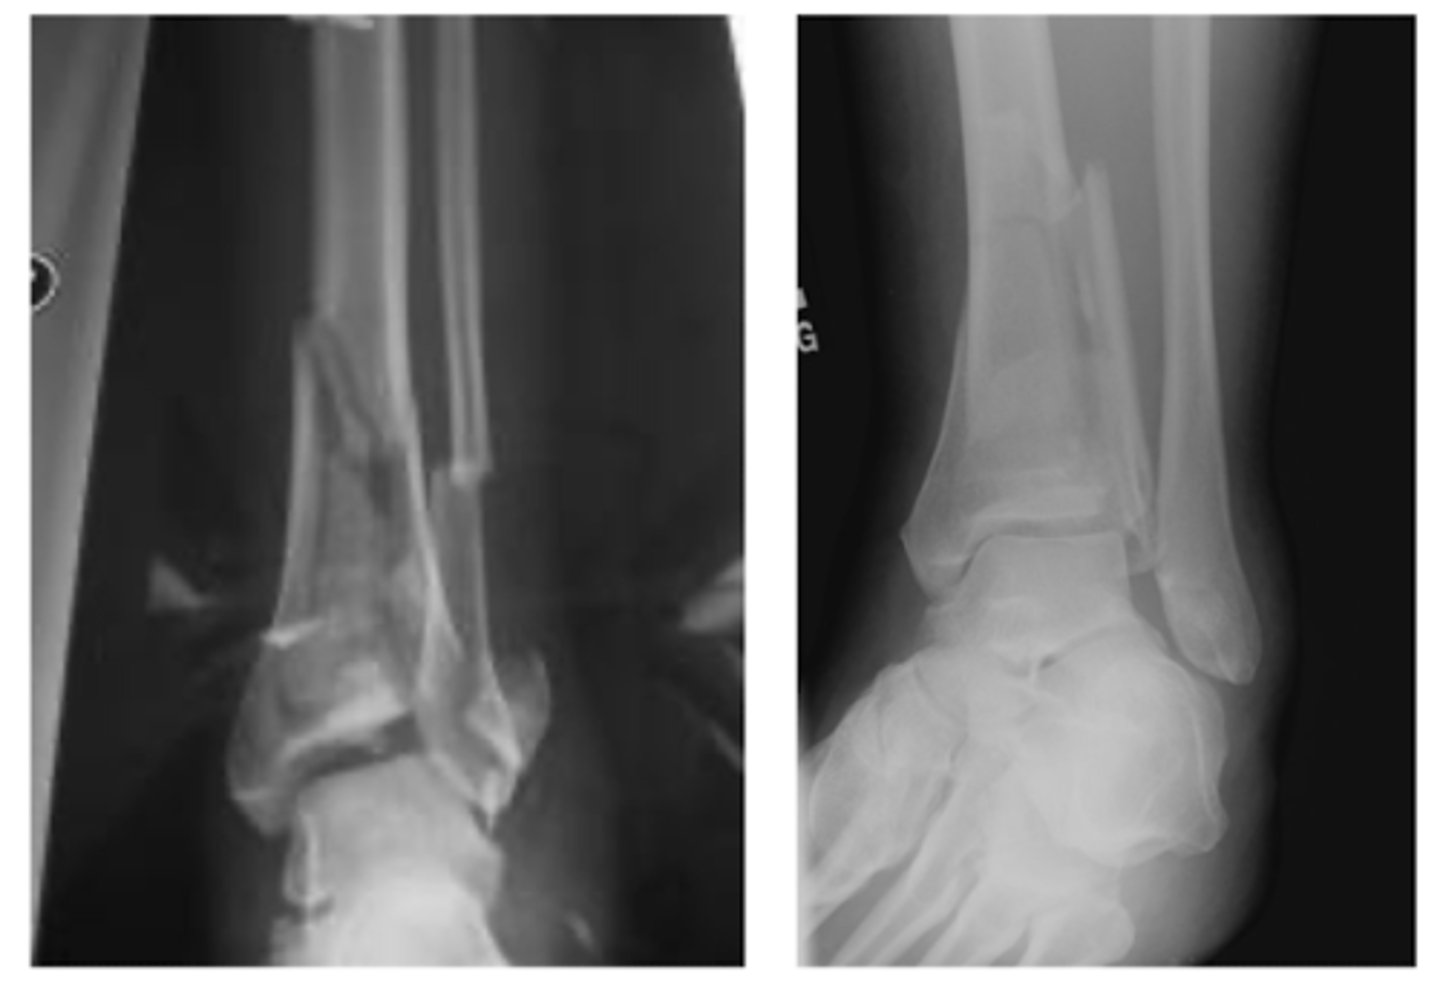

XR of Medial Malleolus Fx.

XR of Lateral Malleolus Fx with minimal displacement.

What is a bimalleolar ankle fracture?

involves BOTH the medial and lateral malleolus

What is a trimalleolar ankle fracture?

involves all THREE malleoli - medial, lateral and

What TWO movements can lead to a Maisonneuve fracture?

pronation

external rotation

What TWO fractures occur together in a Maisonneuve fracture?

Fx of medial malleolus

Spiral fracture of the fibula

What TWO XR findings are consistent with a Maisonneuve fracture?

Tear of the tibiofibular ligament

Widening of the ankle mortise medially